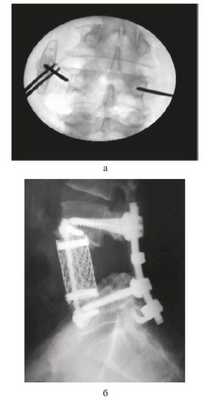

После имплантации протеза и восстановления кровотока начато удаление тела LIV позвонка. Аневризма формировала полость в теле позвонка, которая была заполнена сгустками крови и остатками фиброзной ткани межпозвонковых дисков. Частичное удаление костной массы позвонка не выявило в нем патологических изменений. При гистологическом исследовании удаленного материала — хроническая гематома. После полного удаления остатков кускованием тела позвонка осуществлен передний спондилодез с использованием сетчатого межтелового импланта. Полость имплантата наполнена бикальцифосфатным стимулятором направленного роста кости в виде чипсов Bonemedic (Intrarich) (рис. 4). Рисунок 4. Интраоперационное рентгеновское исследование. Положение импланта Mesh (Medtronic) в области удаленного тела LIV.

Через неделю после стабилизации состояния пациента был проведен второй этап операции — задняя транскутанная транспедикулярная стабилизация системой Viper (De Puy Spine) (рис. 5). Рисунок 5. Интраоперационное рентгеновское исследование. Момент установки транспедикулярных перкутанных винтов (а), боковая спондилограмма (б).